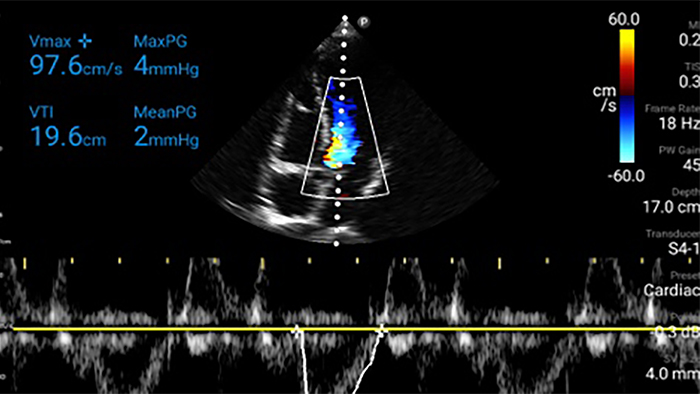

Act faster to protect their heart

When seconds count, portable ultrasound can make the difference. Lumify can provide the high-definition imagery you need whenever and wherever you need it.

Lumify S4-1 broadband phased array transducer